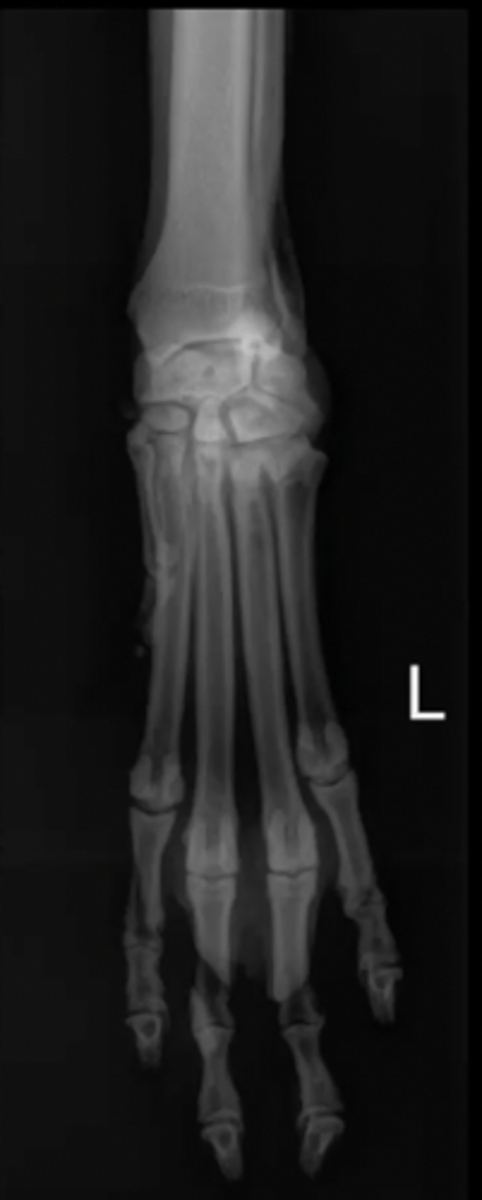

carpus/tarsus/digits

What type of bones might require oblique images?